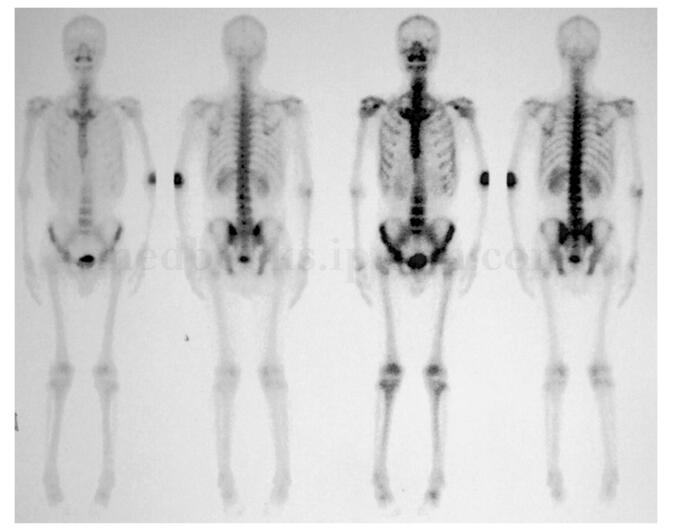

影像学检查:X 线片(图8‐3)和CT(图8‐4)表现为左肘关节前方偏肱骨远端左侧可见类圆形高密度肿块影,边界尚清,与肱骨远端骨皮质间尚有间隙。MRI(图8‐5)表现为左肱骨远端前侧类圆形混杂T 1、混杂T 2信号灶,边界较清,大小约3cm ×3cm ×3cm,增强后呈中度不均匀强化,肱骨远端髓内及前缘骨皮质可见片状低T 1、低T 2信号灶。全身骨扫描(99m Tc‐MDP)(图8‐6)显示为左肱骨远端异常放射性浓集、全身其他部位未见异常放射性浓聚。

图8‐6 全身骨扫描(99m Tc‐MDP)表现